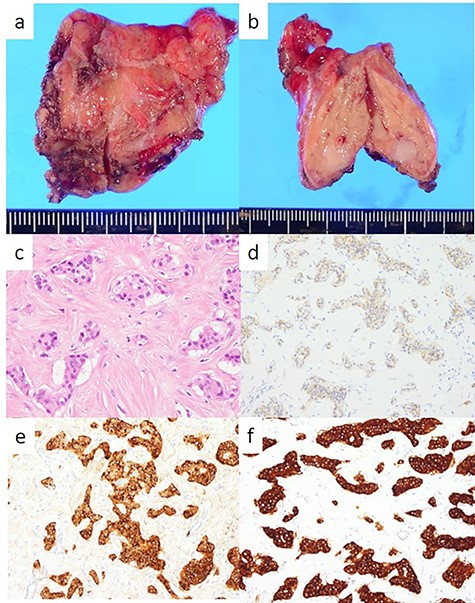

The head tumor was a yellow 38 × 20 × 14 mm solid tumor with capsule, protruding into the duodenum (Fig. 3). Histopathology revealed abundant nests of large clear cells with nested architecture and prominent vasculature (Fig. 3). Immunohistochemistry staining showed positive immunoreactivity for PAX8, suggesting metastasis of RCC (Fig. 3). By contrast, the tail tumor was a white 6 × 6 mm solid tumor with defined cell borders. Histopathology revealed atypical cells with hyperchromatic nuclei in the nests (Fig. 4). Immunohistochemistry showed the following pattern: CD56 (+), chromogranin A (+), synaptophysin (+), Ki67 0.8% (4/489) (Fig. 4). Thus, the tail tumor was diagnosed as a pancreatic neuroendocrine tumor, G1.

Resected specimen and pathological findings of the pancreatic tail tumor; (a, b) a white 6-mm solid tumor in the pancreatic tail; (c) abundant nests of large clear cells (hematoxylin and eosin ×400); (d) immunohistological positivity for CD56 (CD56 stain ×200); (e) immunohistological positivity for chromogranin A (chromogranin A stain ×200); (f) immunohistological positivity for synaptophysin (synaptophysin stain ×200).